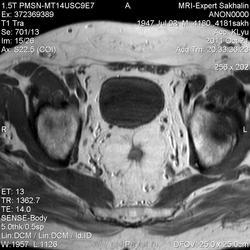

Сегодняшний пациент направлен врачом Онкодиспансера-как обычно без документов, выписок , результатов исследований)))Перенес операцию по удалению опухоли прямой кишки , наложена колостома.

Зато вопросы в направлении:1Протяженность опухоли.2.Depositae in hepar.3Мезоректум.При этом назначил только малый таз....

Прошу помощи!Во-первых, не совсем понятная простата и мочевой пузырь; на некоторых сканах есть признаки тесного прилежания простаты к стенке кишки.В общем-я ничего не понимаю-что удалили!

Признаков распространения опухоли в мезоректум я не вижу (наружный контур кишки четкий, ровный), простата и апоневроз Денонвилье интактны. А в мочевом скорее всего утолщенная межмочеточниковая складка попала в срез .Элевация простаты в мочевой пузырь? Нужны короналы с мочевым пузырем и ПЖ.

Ольга Сергеевна, я завтра у направляющего врача узнаю.Простата гиперплазирована, но прорастания достоверно не вижу.Мезоректум, кажется, тоже интактен.Спасибо за комментарий!